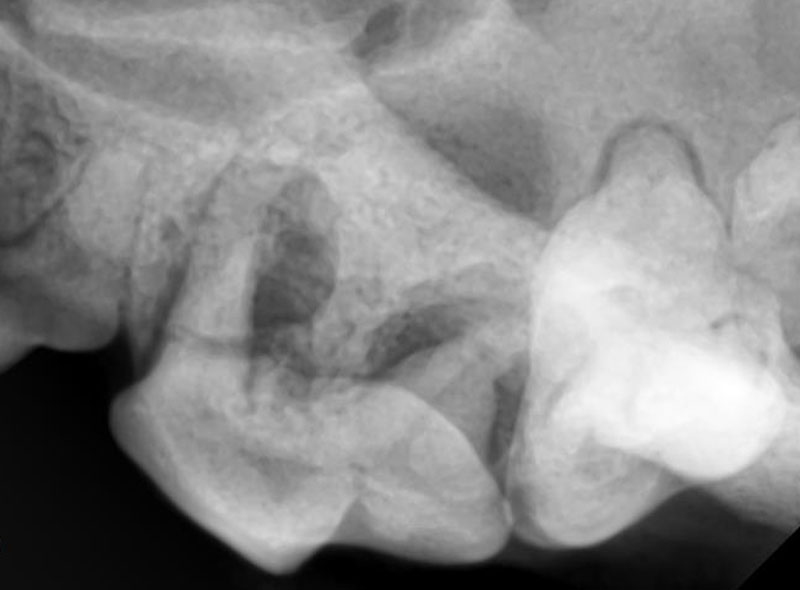

顔面の骨を溶かす疾患(根尖周囲病巣、口腔鼻腔瘻)

-

上顎第4前臼歯の歯根部分周囲の骨が大きく溶けています。

破折による根尖病巣。病巣の直上の皮膚に穴が開いて、排膿します。

抜歯をしない限り、これは治癒しません。 -

犬の犬歯の根っこは、鼻腔に数mmの骨で接しているため、歯周病により周囲の骨が溶かされるほどになった場合や、鼻水やくしゃみが出ます。

口腔鼻腔瘻。犬歯のポケットが深くなると、鼻腔内に通じて、くしゃみや鼻血などが見られます。

症状

くしゃみ、鼻水、鼻血(口腔鼻腔瘻)、頬や鼻、下顎などが腫れる、目やにや結膜の充血など(根尖周囲病巣)、顔面周囲の皮膚に炎症を起こしたり排膿する(外歯瘻)

治療